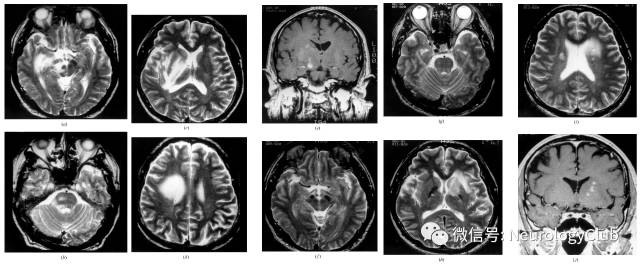

神经白塞病包括实质型和非实质型。实质型神经白塞病约占70-80%,病灶以脑干(脑桥、中脑)常见,也可延伸累及间脑、基底节区。累及大脑半球时,常为多发的小白质病变,也可表现为孤立性类瘤样病灶。脊髓受累时可见单发或多发的不同长度的炎性病变,常位于颈胸髓。也可有脑膜脑炎,表现为脑膜强化。急性期病灶在T1WI上呈等-低信号,增强通常为片状强化,也可出现环形强化,T2WI和FLAIR上为高信号,DWI上高信号,相应ADC值降低。部分病灶中心或周围可见出血。累及脊髓时横断面T2WI可见“百吉饼(在美国纽约较为流行,也称硬面包圈)征(Bagel Sign)”。慢性期,病灶多缩小,通常无强化,可见脑萎缩,尤其是脑干。

(图16:A-B:典型实质病变,从间脑延伸至基底节;C:多发性硬化样病灶;D:非特异性白质病变)

(图17:a-d:T2WI可见右前中脑,中脑腹侧被盖区,基底节,内囊后部,外囊和脑室旁白质弥漫或斑片状高信号病灶;e:右侧内囊后部和基底节可见斑片状强化病灶;f-j:随访3年复查MRI可见右侧大脑半球和脑干原T2WI高信号病灶明显好转,但左侧出现新发病灶)

(图18:FLAIR可见皮质下白质受累,貌似脱髓鞘病变)

(图19:可见弥漫对称白质病变伴脑干受累)